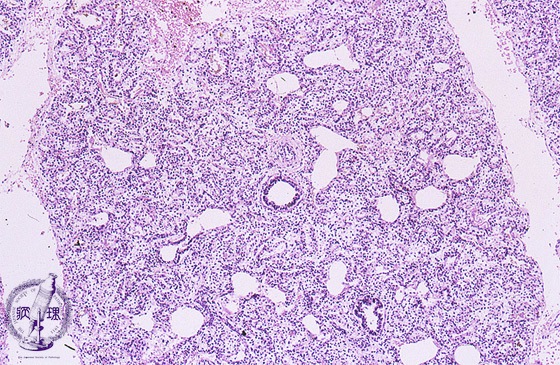

Microscopic view (HE stain, low power view): Appearance of atelectasis in a stillborn infantfs whose lungs never expanded.

Click the image to see the enlarged image.

• There is no guidance by arrows.